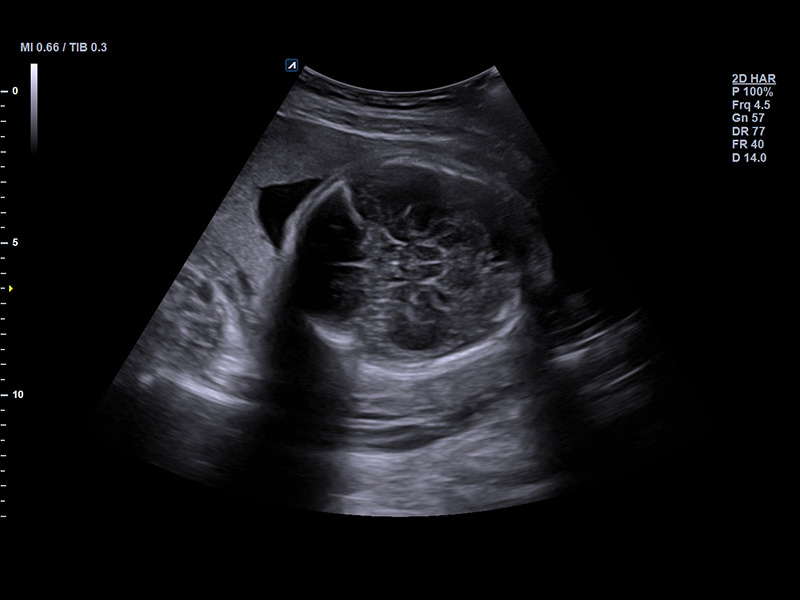

SC2-11H

X+ Crystal Signature™ Microconvex(2~11MHz)

Application:

Abdomen, Pediatric, OB/GYN, Urology, EM